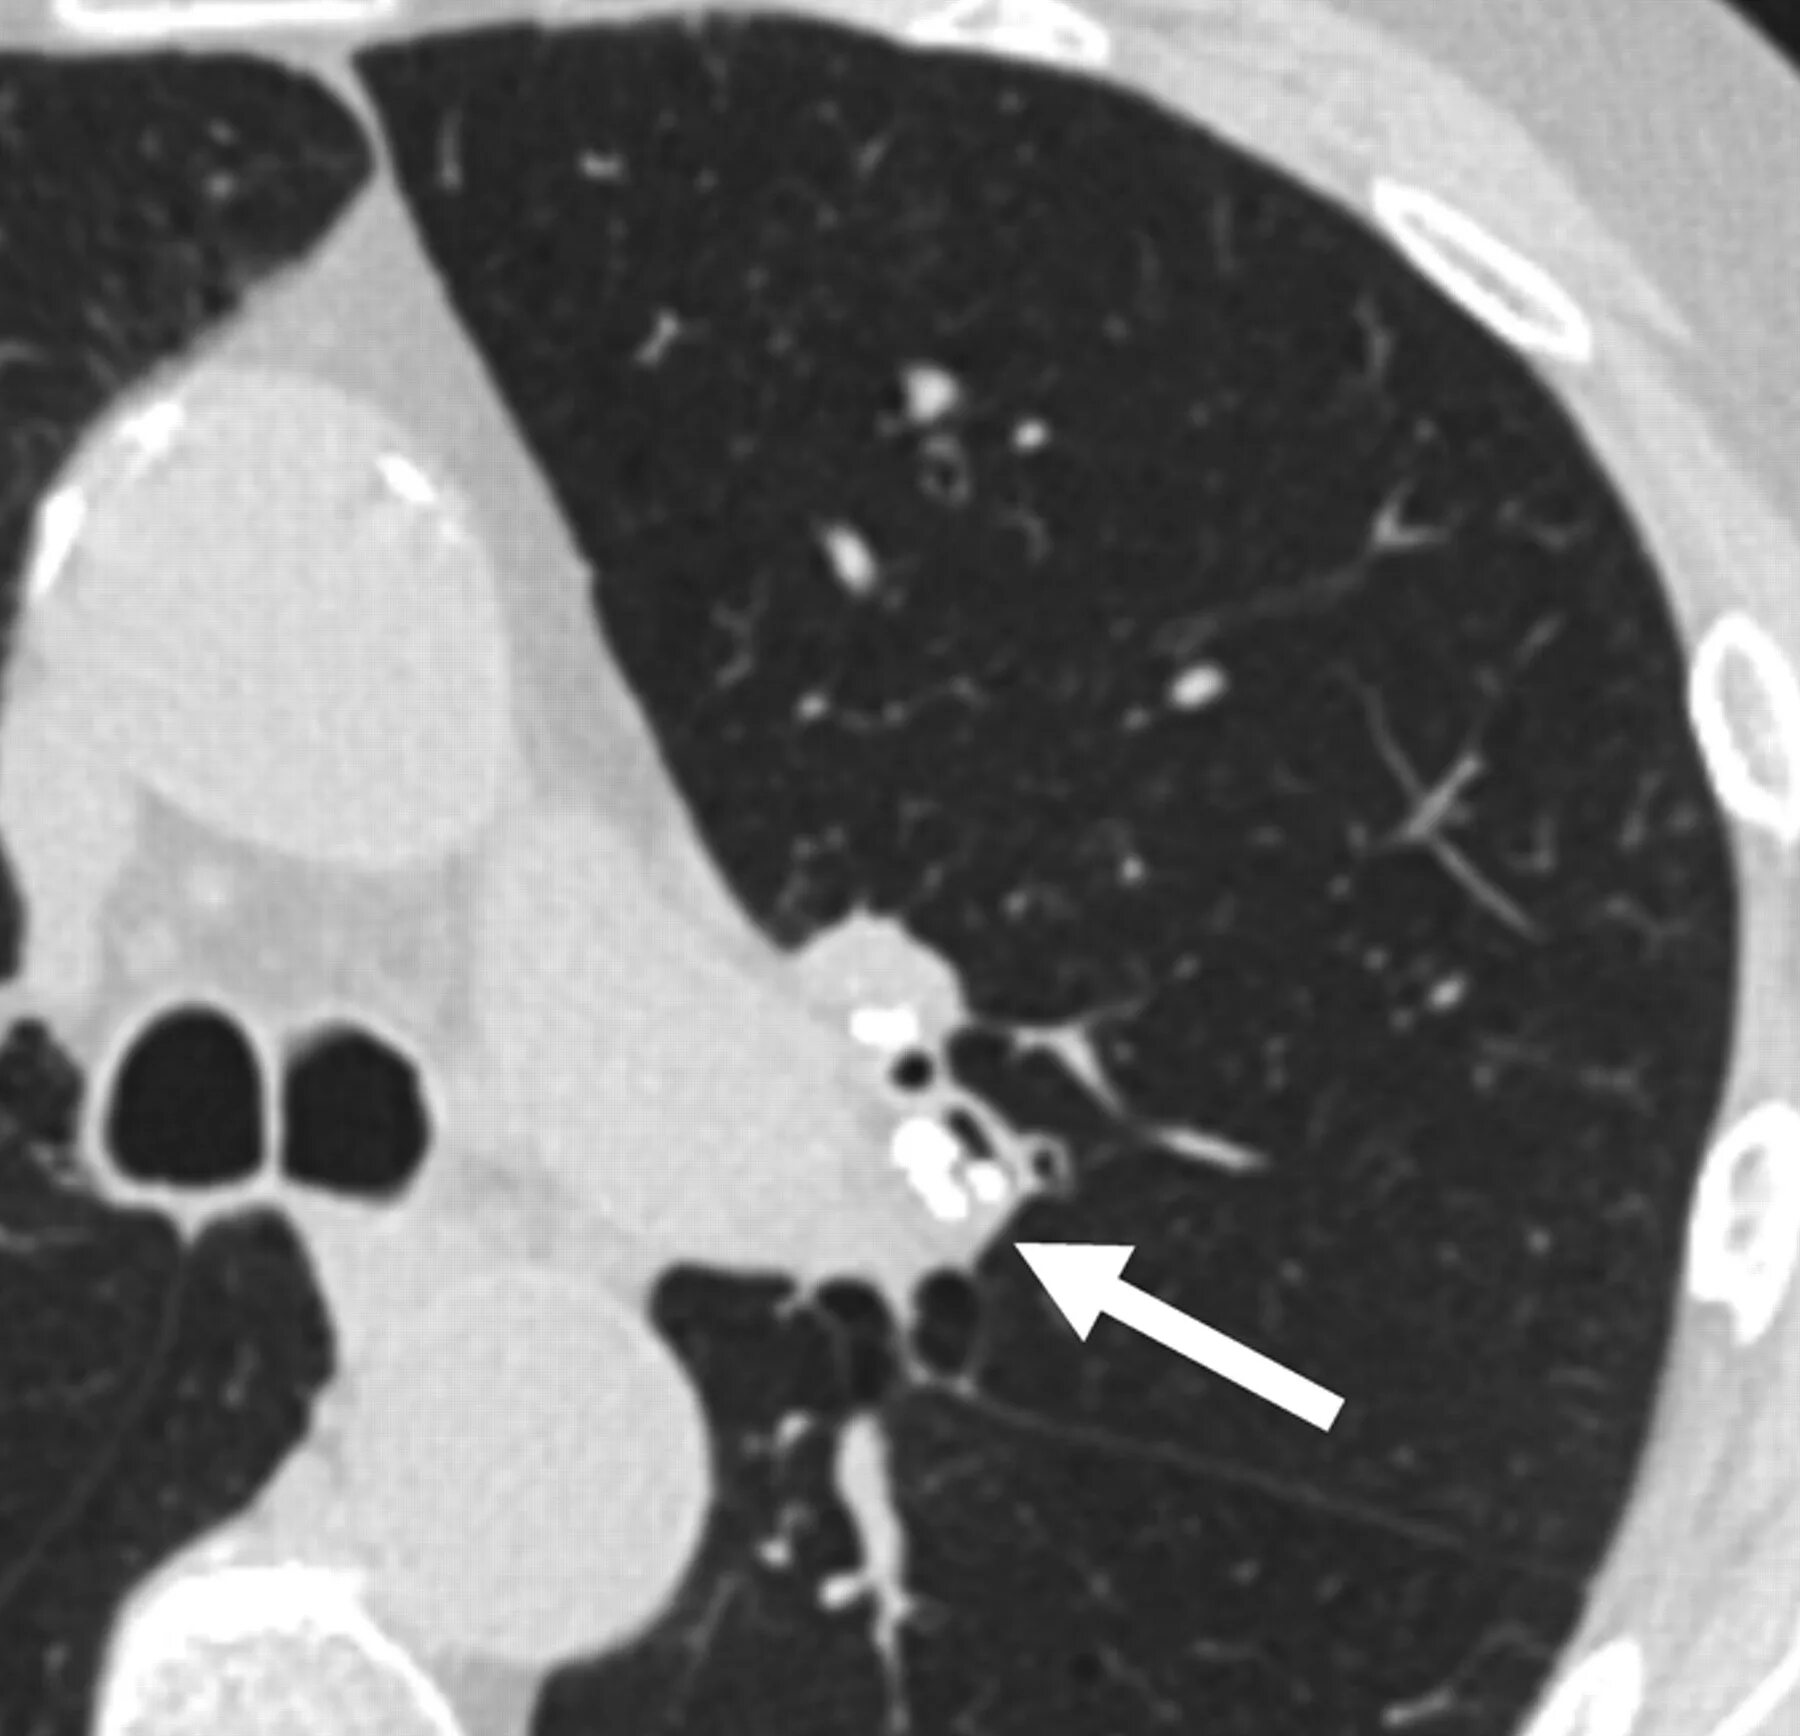

Утолщение бронха